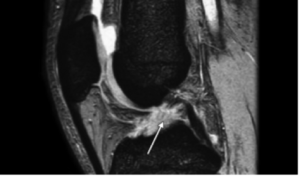

• ACL Reconstruction